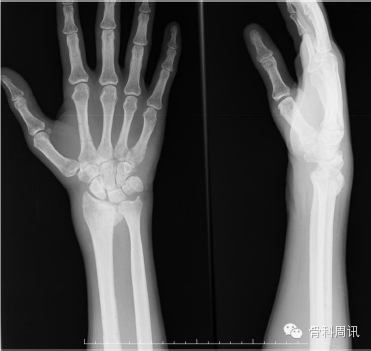

術後第一天鼓勵患者主動進行手指活動。皮膚愈合已無大礙。術後6周,患者已康複並能主動活動,於是拆除固定支架和克氏針。隨訪中,患者的正中神經功能障礙持續了6個月,手部肌肉明顯出現萎縮。術後6個月,該患者恢複工作。在第一年的隨訪中,患者的活動範圍為:30-45°屈曲,0-10°擴展,45°旋前,45°旋後。患者的手腕評分(PRWE)為疼痛15分和功能35分,最終得分為50分,恢複情況良。在第一年隨訪中,第1、2、3根手指的感覺麻木已緩解,但手部肌肉仍然輕度萎縮。X片顯示橈腕關節背側發生輕度脫位和尺骨發生輕度轉化(圖8)。

Fig. 8. First year follow up, with minimal dorsal and ulnar translation.

圖8 第一年隨訪中,背側和尺骨輕度轉化。